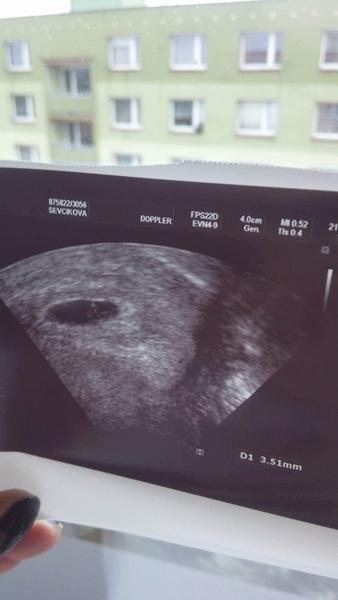

@korunka23 ja sla na prvni prohlidku kdyz jsem byla 5+3tt a foto z urz mam takove 🙂 Takze brzy urcite neni 🙂 a gratuluji 🙂

@korunka23 tak ono bude brzy a nebude záleží kdy jsi měla ovulku já jí třeba měla o týden později šla sem podle ms 6+4, aby bylo srdíčko, ale byla jsem asi jen 5+4 takže byla jen dutinka a teď půjdu po 3 týdnech takže docela dlouhá doba a mám strach, aby vše bylo ok ☹